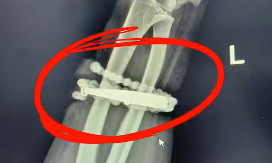

通过手术操作,医生们成功将手镯和串珠从厚厚的增生组织中完整剥离出来。